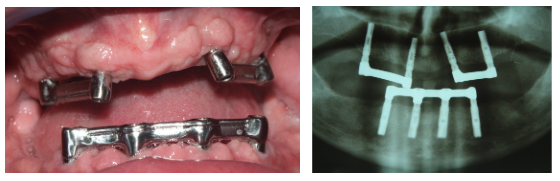

Estructura Subperióstica con carga inmediata maxilar

Paciente con atrofia total del hueso del maxilar que precisa rehabilitación. Se le realizó tratamiento con estructura subperióstica y el mismo día se le colocaron unos dientes fijos provisionales sobre la estructura.

Foto de las barras que portan las prótesis, y de la ortopantomografía de control 10 años después de su colocación.